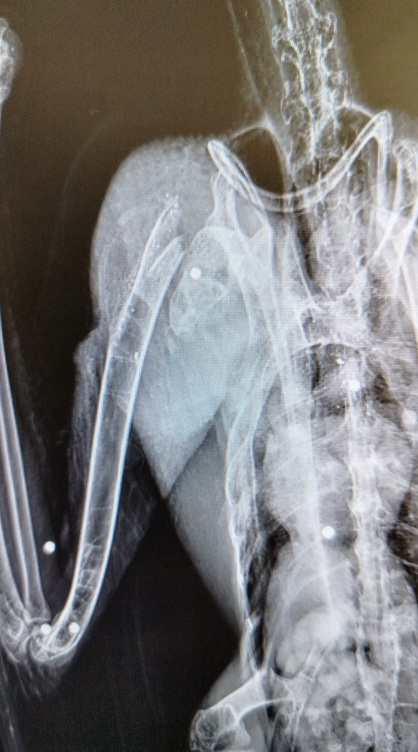

PESCARA - Sono passati pochi giorni dallo stupore espresso per il meraviglioso volo di una coppia di Ibis eremita nelle campagne del pescarese. La specie è venerata nell’antico Egitto come divinità della scrittura, della conoscenza e del tempo, ma purtroppo se ne contano non più di mille esemplari. Purtroppo un colpo di fucile esploso da un bracconiere ha fermato il volo. Il giovane Ibis eremita abbattuto da una fucilata in contrada Mirabello di Penne è stato trovato in un pollaio dove probabilmente cercava il suo compagno di viaggio. Il CRAS Lago di Penne si è attivato tempestivamente avviando una procedura di urgenza richiedendo subito una radiografia che ha rilevato la presenza di numerosi pallini da caccia nel corpo del rarissimo animale protetto. È stato operato con successo nell’ambulatorio veterinario vestino di Antonazzo Giammaria. L’intervento chirurgico delicato e difficile ha avuto successo grazie alla tempestività dell’intervento ed alle buone condizioni fisiche dell’esemplare recuperato a poche ore dall’abbattimento.

L’ibis eremita è uno degli uccelli più affascinanti e rari d’Europa. Il suo aspetto inconfondibile, piumaggio nero iridescente, testa calva di colore rosso e lungo becco ricurvo, lo rende immediatamente riconoscibile, ma è soprattutto la sua storia millenaria a renderlo speciale. L’ibis eremita (Geronticus eremita) è uno degli uccelli più simbolici e fragili del nostro tempo. Abitava vaste aree dell’Europa meridionale, del Nord Africa e del Medio Oriente. Oggi sopravvive solo grazie a piccoli nuclei residui e a complessi progetti di conservazione. L’ibis eremita è in pericolo a causa di una caccia (bracconaggio) scellerata e inutile, e per i disturbi nei siti di nidificazione che hanno causato un declino drammatico, portando la specie sull’orlo dell’estinzione. Negli ultimi decenni, l’ibis eremita è diventato un emblema della biodiversità piú minacciata. La sua sopravvivenza non è più affidata solo alla natura, ma anche alla responsabilità umana. Programmi di reintroduzione e tutela, soprattutto in Europa e in Nord Africa, hanno permesso una lenta ripresa, ma la specie resta estremamente vulnerabile. Parlare dell’ibis eremita oggi significa riflettere sul rapporto tra uomo e ambiente, sulla possibilità di riparare, almeno in parte, ai danni del passato e sulla necessità di una convivenza più consapevole con le altre forme di vita che condividono il nostro pianeta, anche se, purtroppo, molti esemplari vengono inesorabilmente abbattuti dai bracconieri italiani ogni anno. È accaduto nelle regioni del Nord Italia ma anche in Abruzzo, nella terra dei Parchi. Due esemplari di Ibis eremita provenienti dalla Germania hanno sostato per oltre due mesi sulle colline argillose del pescarese a valle del Parco Nazionale del Gran Sasso e Monti della Laga nei dintorni della Riserva Naturale Regionale Lago di Penne, Oasi del Wwf Italia. Le prime immagini del fotografo Sandro Ginaldi che hanno accertato la presenza dei rari uccelli nel Lago di Penne risalgono al 27 novembre 2025. Da allora numerose segnalazioni lungo il bacino del Tavo hanno rilevato la presenza costante dei rarissimi e innocui ibis. Fino a ieri quando un cittadino consapevole ha raccolto uno dei due esemplari feriti portandolo al CRAS Lago di Penne. Il Centro di recupero animali selvatici gestito in collaborazione con il Parco Nazionale del Gran Sasso e Monti della Laga, il Comune di Penne, i Carabinieri Forestali dell’UTB di Pescara, la Riserva Regionale di Penne e la Cogecstre, si è subito attivato portando il giovane esemplare di Ibis eremita in uno studio veterinario specializzato che ha subito rilevato la rottura dell’omero all’altezza della cintura scapolare ed ha effettuato un delicato intervento chirurgico per tentare di restituire all’ala le migliori funzioni per permettere all’Ibis di tornare a volare. Sono stati allertati anche il Nucleo Carabinieri Cites che effettueranno le dovute indagini sul folle atto di bracconaggio cercando di verificare se l’altro esemplare inseparabile Ibis di nome “Coccole”, con l’anello numero 751 sia riuscito a sopravvivere.